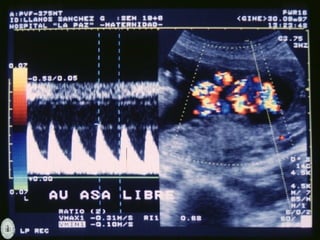

DOPPLER COLOR

- Detecta presencia y

dirección del flujo en un

vaso

- Diferencia flujo laminar o

turbulento

- Valora grado de resistencia

que el flujo tiene que vencer

Doppler de arteria cerebral media:

polígono de Willis